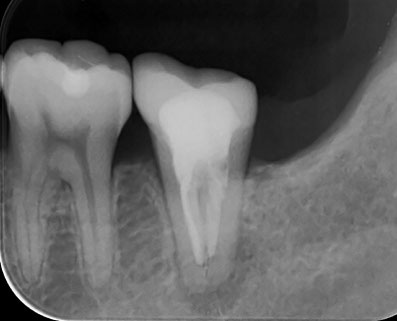

術後5年経過症例。樋状根は抜歯と判断されることが多いようですが、当院ではあきらめずに治療して良い成績を残しています。(7番の近心には、金属修復物下に虫歯があります。他院で定期健診を受けていたようですが、メンテナンスの仕方に問題はなかったでしょうか?)

約1ケ月後ですが、根の先の炎症の証である透過像は、消失し、噛むと痛いなどという臨床症状も消えました。